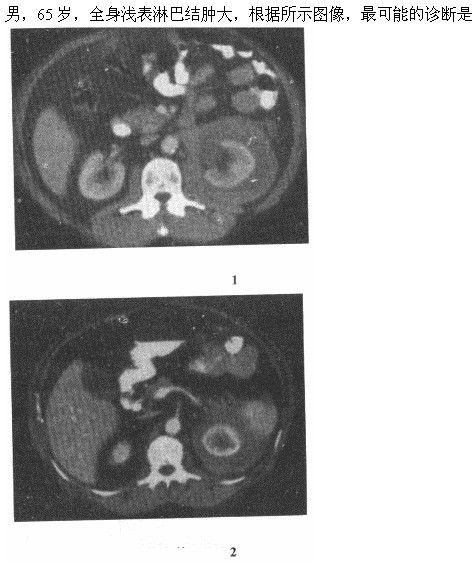

A.左侧肾癌

B.左肾转移癌

C.淋巴瘤左肾周浸润

D.左肾外伤出血

E.尿外渗